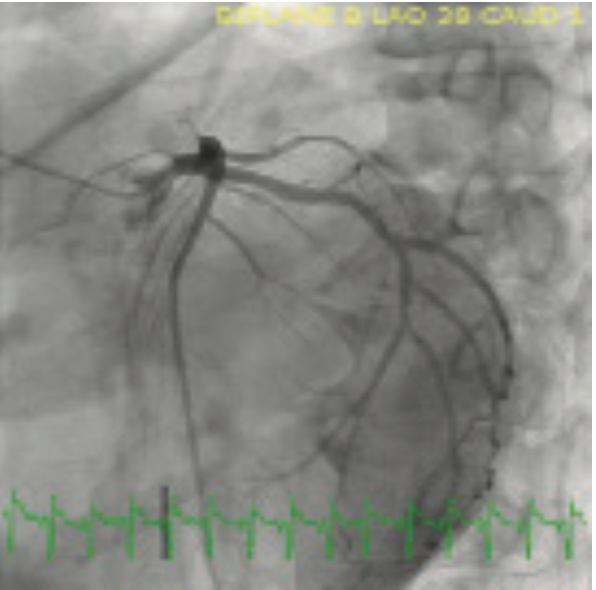

The CardioMEMS HF system (Abbott) provides ambulatory monitoring of pulmonary artery pressures and reduces hospitalization for heart failure. Cardiac resynchronization therapy is indicated for patients with heart failure, cardiomyopathy, and a left bundle branch block on electrocardiography. While the CardioMEMS is typically implanted via a femoral venous sheath, we describe implantation via the axillary vein at the time of biventricular defibrillator implantation.